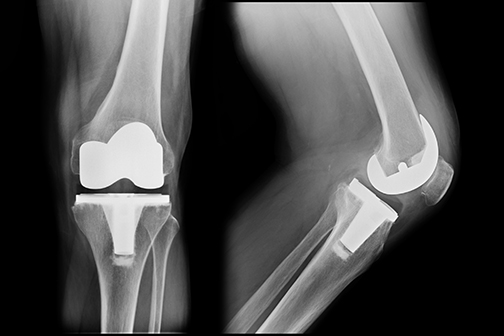

LSU Health New Orleans Pain Protocol Eliminates Need for Opioids Following Knee Replacement in Most Patients

A study led by Vinod Dasa, MD, Professor of Orthopaedics at LSU Health New Orleans School of Medicine, reports that a novel surgical pain management strategy following total knee arthroplasty (TKA), or total knee replacement, provided pain relief without opioids. The researchers also found that changing prescriptions for opioids at discharge from automatic to upon request dramatically decreased opioid use. More

LSU Health New Orleans Study Reports Majority of Patients Recover from Knee Replacement Without Opioids

A retrospective case series study led by Dr. Vinod Dasa, Professor of Clinical Orthopaedics at LSU Health New Orleans School of Medicine, reports that more than two-thirds of the patients who underwent total knee replacement did not need opioids for postoperative pain. Results are published in the Journal of Orthopaedic Experience & Innovation. More